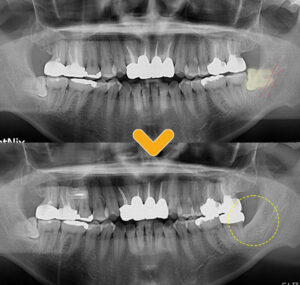

이렇게 누워있는 사랑니의 경우

힘을 주어 무리하게 뽑기보다는,

조금씩 치아를 부수면서

조각내어 발치하는 형식으로 진행됩니다.

하지만 복잡 수술 발치의 경우

환자분처럼

치아가 완전히 누워있어 가로방향이고,

잇몸 뼈 속에 있으면서 간단히 발치하기 어려워

사랑니 절단이 필요합니다.